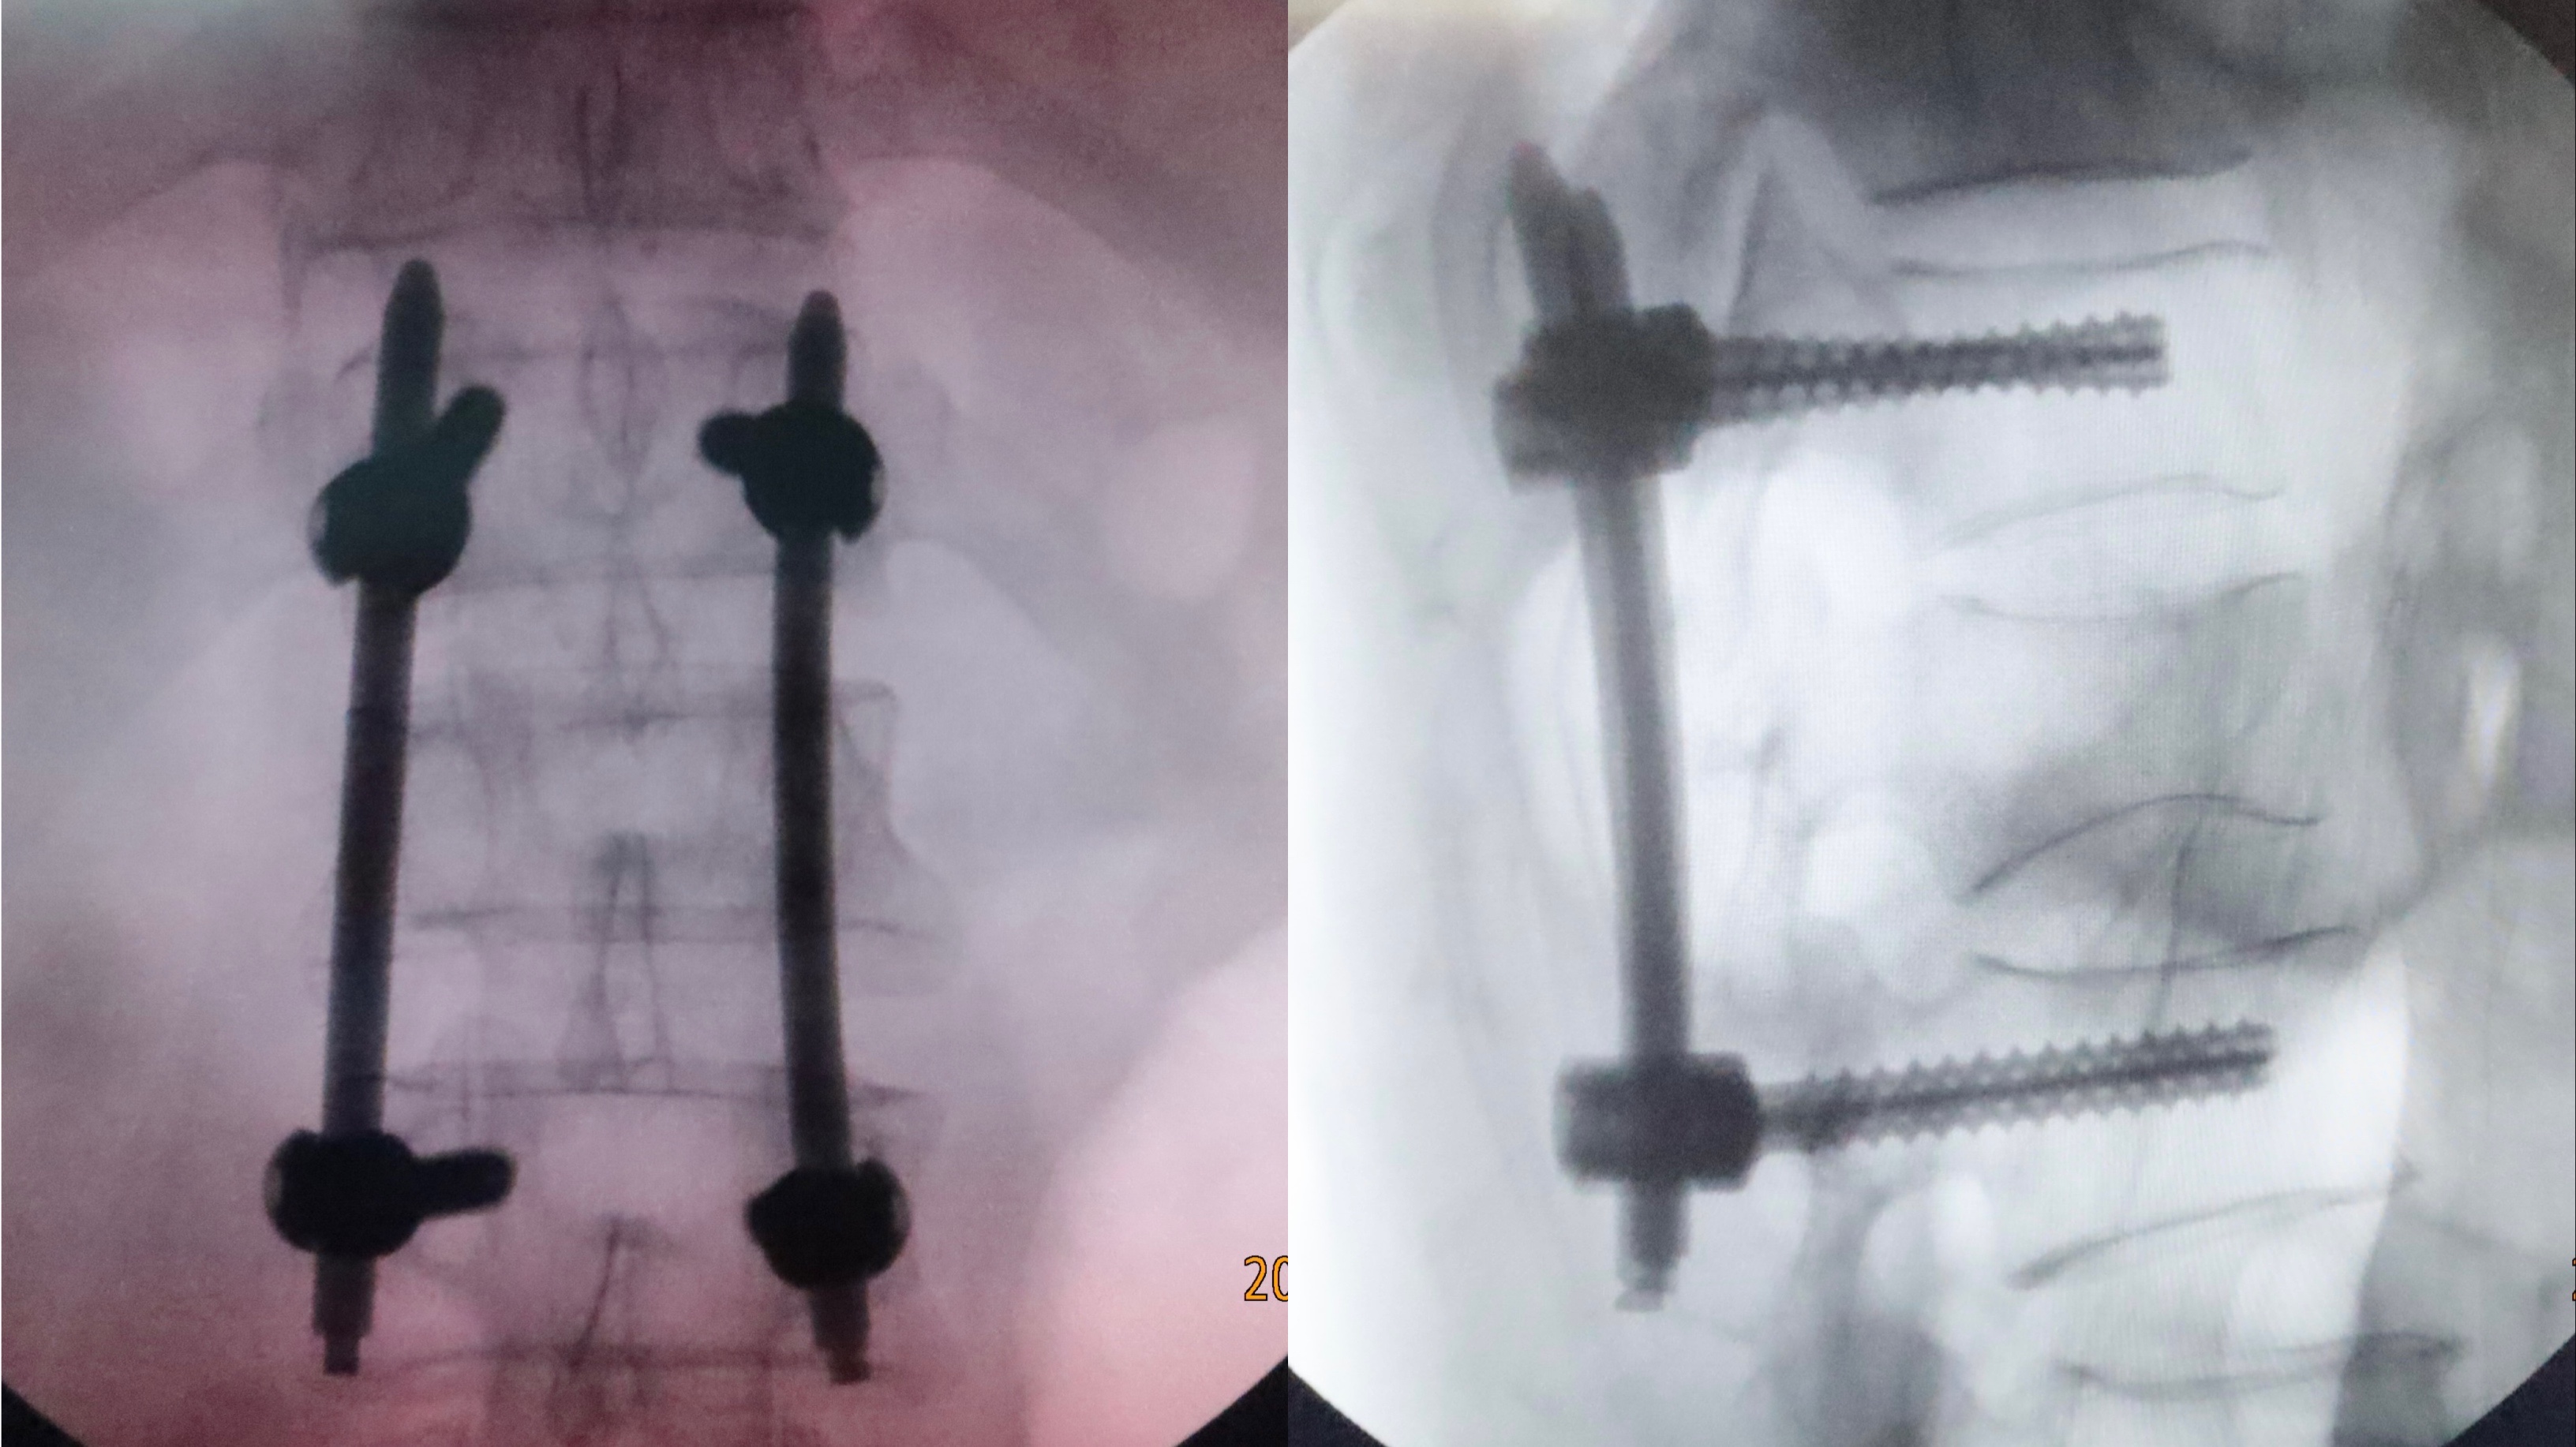

(术后复查显示:内固定位置良好。)

59岁的长沙居民张先生因外伤导致腰1椎体骨折,磁共振检查提示:不仅存在椎体压缩,还合并了相应层面椎管轻度狭窄及马尾神经损伤征象。经过盛斌主任团队综合评估后,于8月1日为其实施机器人辅助下经皮脊柱椎弓根螺钉内固定手术。手术过程十分顺利,在机器人辅助下的置钉方式也比传统方法准确性更好、安全性更高、用时更短,加之微创手术出血极少,患者术后即可早期下床活动,患者及家属对此赞不绝口。